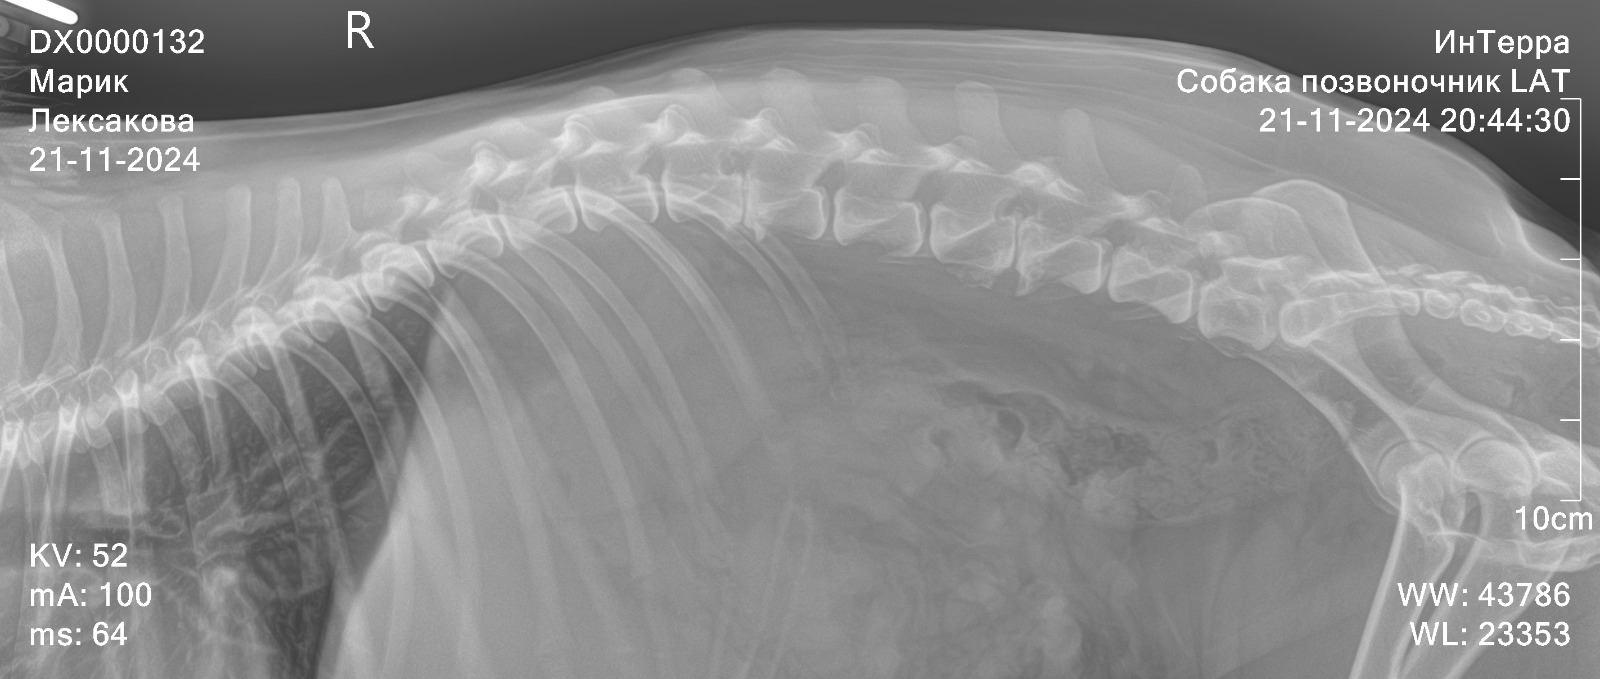

Рентген позвоночника

Вложения

IMG-20241121-WA0054.jpg

IMG-20241121-WA0047.jpg

IMG-20241121-WA0045.jpg

IMG-20241121-WA0034.jpg

IMG-20241121-WA0041.jpg